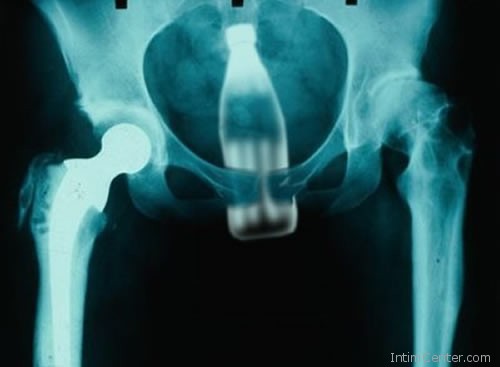

– Ami kézzel fogható, abban előbb-utóbb valaki meglátja a lehetőséget és felhasználja szexuális céljaira. Egy időben nagy sláger volt a dezodoros flakon, amit ha kupakkal felfelé dugtak be, gyakran anélkül húztak ki. Az uborka, répa, babán, fogkefe már szinte rutinmunkát ad. Arra is emlékszem, amikor egy fiatal fiú félt, hogy a kábítószeres tasakok kipukkannak a gyomrában, ezért kitalálta, hogy azokat ketchupos üvegbe rejti és alulról felhelyezi. Az akció előtt főpróbát tartott, de az üveg beszorult és a sebészeten kötött ki – meséli egy műtős.

– A gyerekkorban előforduló, az orrba feldugott és lenyelt játékdarabok említésre sem méltók. Mert amit le lehet nyelni, azt le nyelik a felnőtt emberek is. Több, mint harminc éve dolgozom az egsészségügyben, sokat láttam. – árulta el lapunknak egy nevét nem vállaló egészségügyi dolgozó, majd sorolni kezdte a „megevett” tárgyakat – A nagyobb méretű élelmiszerek általában véletlenül kerülnek a gyomorba, ide sorolnám a fogpiszkálót is. Az egy darabban lenyelt héjas burgonya, mandarin, narancs azonban már elgondolkodtató. Volt, aki lenyelte a kanalat, kést, villát és ki kellett operálni a gyomrából, de a miértre nem tudott választ adni. Láttam már fésűt, hullámcsatot, műkörmöt, tollat, zoknit és kulcsot a röntgenképeken. A rabok általában pengét szoktak lenyelni, hogy ha csak pár napra is, de kiszabaduljanak a cellájukból.